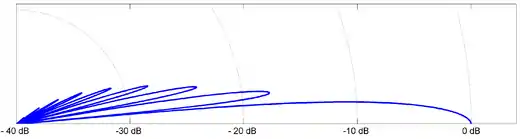

To illustrate the phenomena of side lobes in ultrasound beams, the resulting directivity function and acoustic intensity is calculated for a 1 MHz beam transmitted into water using a 1 cm radius transducer. Figure 2 plots the Directivity function, while Figure 3 plots the acoustic intensity relative to the intensity at the transducer surface.

For the purposes of diagnostic and therapeutic ultrasound the presence of side lobes is an undesirable effect. In diagnostic imaging wave reflection originating from the side lobes can be misinterpreted as reflections from the main beam, and act to reduce the resulting image quality. In therapeutic applications, side lobes represent energy dissipation on regions not intended to be effected. To reduce the effects of side lobes, ultrasound devices use transducer designs based on beamforming theory, making the analysis substantially more complicated than the simple cylindrical transducer discussed. One technique to reduce side lobes is the use of a phased array to focus the main at a particular depth, thus reducing the relative magnitude of side lobes. Another technique known as acoustic shadowing reduces side lobes by emitting lower amplitude waves near the edge of the transducer. As will be discussed in a proceeding section, an emerging technique to enhance focusing and reduce side lobes is the purposeful consideration of nonlinear acoustic effects in ultrasound beams.[1][11]